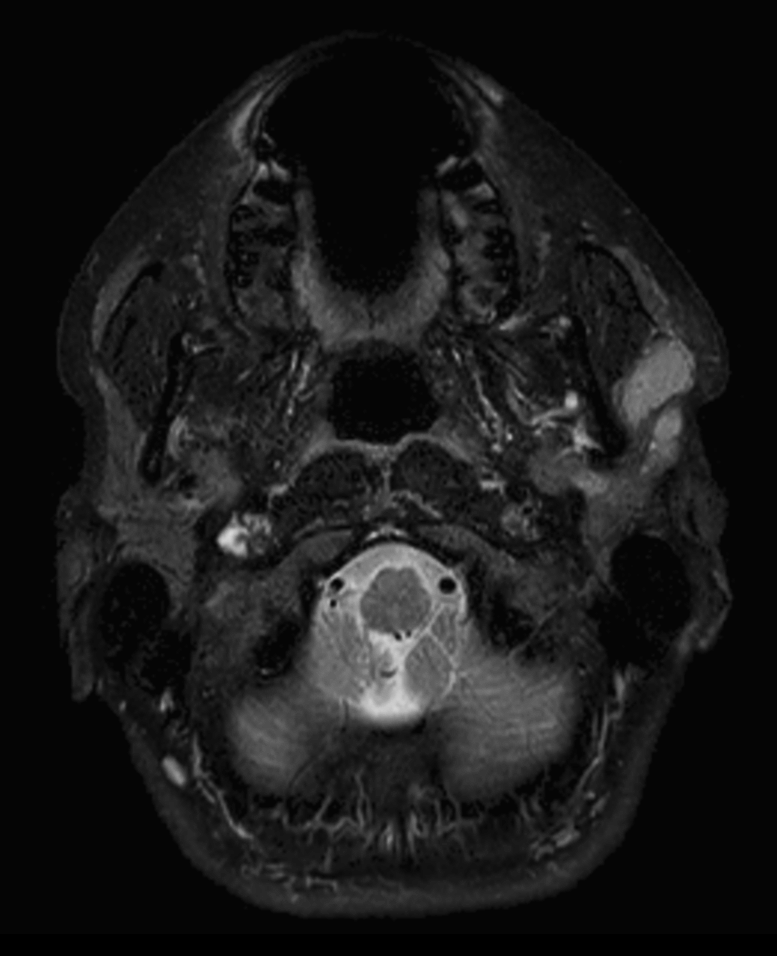

Axial T1w TSE